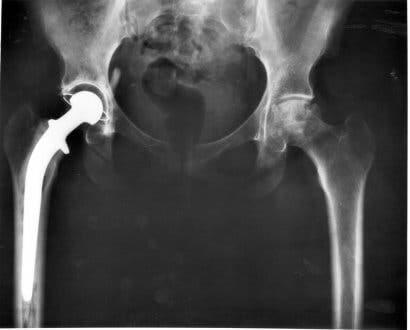

- Total höftplastik. Med detta ersätter man den naturliga leden med en form gjord av syntetiska material.